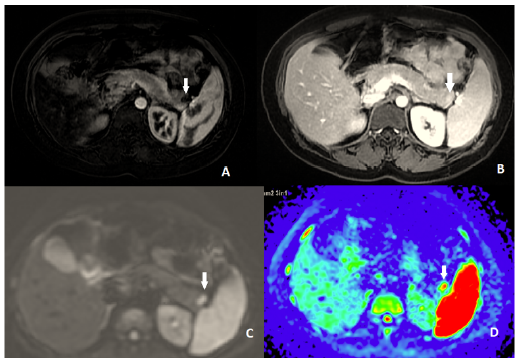

Intrapancreatic Accessory Spleen Masquerading as a Neuroendocrine Tumor

Yassine Zerhari, Hatim Essaber, Mohammed Ennmer, Asaad El Bakkari, Soukaina Allioui, Hounayda Jerguigue, Youssef Omor and Rachida Latib. 10(7):03-05.